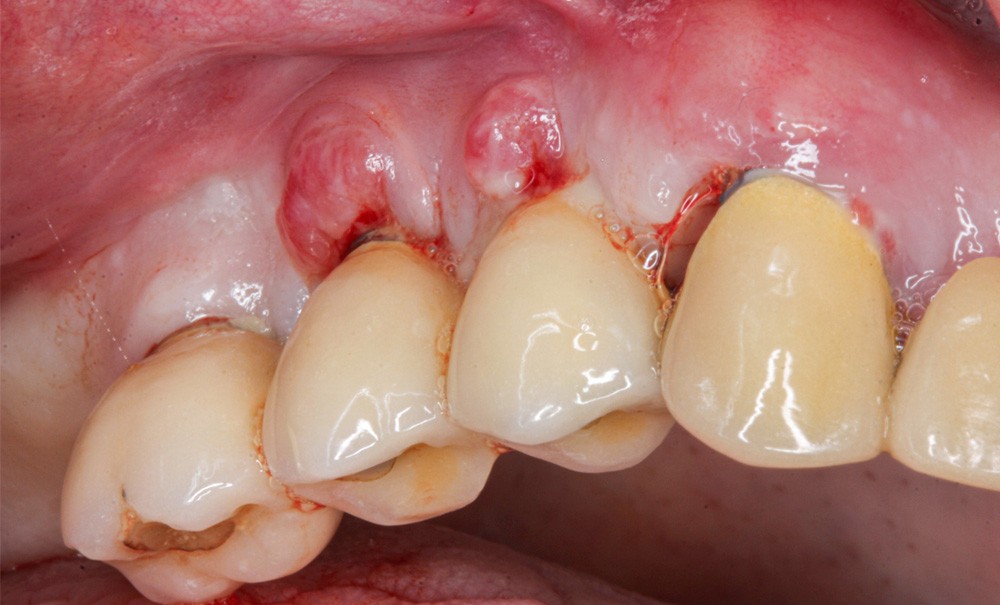

Parmi les complications rencontrées en implantologie, le taux de mucosite atteindrait 43 % des patients, et le taux de péri-implantites s’établirait à 22 % [2]. Elles concernent un grand nombre de patients [3]. Les récessions péri-implantaires, qu’elles soient associées ou non à une péri-implantite [4], représentent également une complication biologique, dont la prévalence serait de 16,9 % [5]. Enfin, des complications mécaniques, comme des fractures de vis ou de suprastructure, ou des dévissages d’éléments prothétiques [6] peuvent aussi exister.

Toutes ces complications peuvent aboutir à la dépose de l’implant, ou explantation, et posent à ce titre un challenge pour les cliniciens : la décision de conserver un implant ou non est aujourd’hui basée sur des opinions d’expert et sur le sens clinique de chaque praticien [7]. Pour évaluer la conservabilité d’un implant pathologique, le clinicien évalue d’abord son pronostic, c’est-à-dire la prédiction de l’issue de la maladie [8]. Or, les modèles de pronostic de traitement des complications implantaires sont rares, et la question bénéficie encore à ce jour de peu de travaux. Le but de cette revue de littérature est d’identifier les modèles existants, et de proposer un arbre décisionnel pour l’explantation ou la conservation des implants.